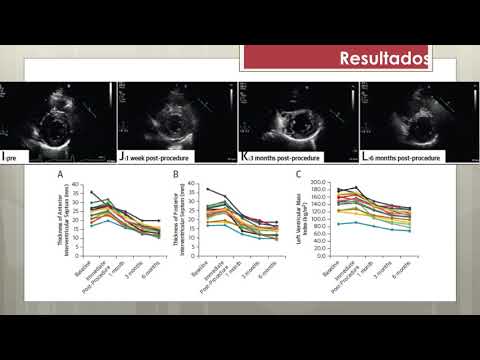

Ablación septal de miocardiopatía hipertrófica obstructiva. Dra. Sofia Gabriela Rodríguez. Residencia de Cardiología. Hospital C. Argerich. Buenos Aires